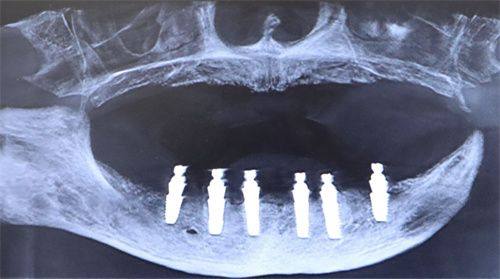

一家医院的技术水平较大程度上取决于医生团队。成都团圆口腔医院拥有一支实力强大的医师队伍。这些医生不仅具备扎实的专精知识,还有着丰富的临床经验。他们擅长种牙、正畸等多个领域。在种植牙方面,医生们能够根据患者的不同情况,制定个性化的种植方案,采用精良的种植牙技术,确保种植成效稳定、美观。在正畸领域,医生们可以正确分析患者的牙齿情况,选择合适的矫正方式,帮助患者拥有整齐洁白的牙齿。例如,对于一些复杂的口腔病例,医生们会通过多学科会诊的方式,为患者提供良好质的治疗方案。